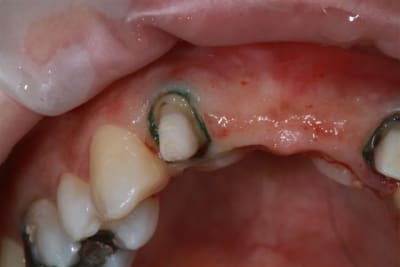

Donc dans un premier temps,je décide d'essayer de retraiter 12/22, de toute façons ça ne peut pas être pire que ce qui tiens depuis 10 ans... enfin 12 mobilité quasiment 3.

ensuite Srew post (bouh...) et résine, afin de pouvoir poser un provisoire et réfléchir à l'avenir du parodonte...car il va y avoir un problème quelle que soit la solution choisie.

la suite

reconstitution, taille pour empreinte et provisoire (pas beau mais il sera remplacé)